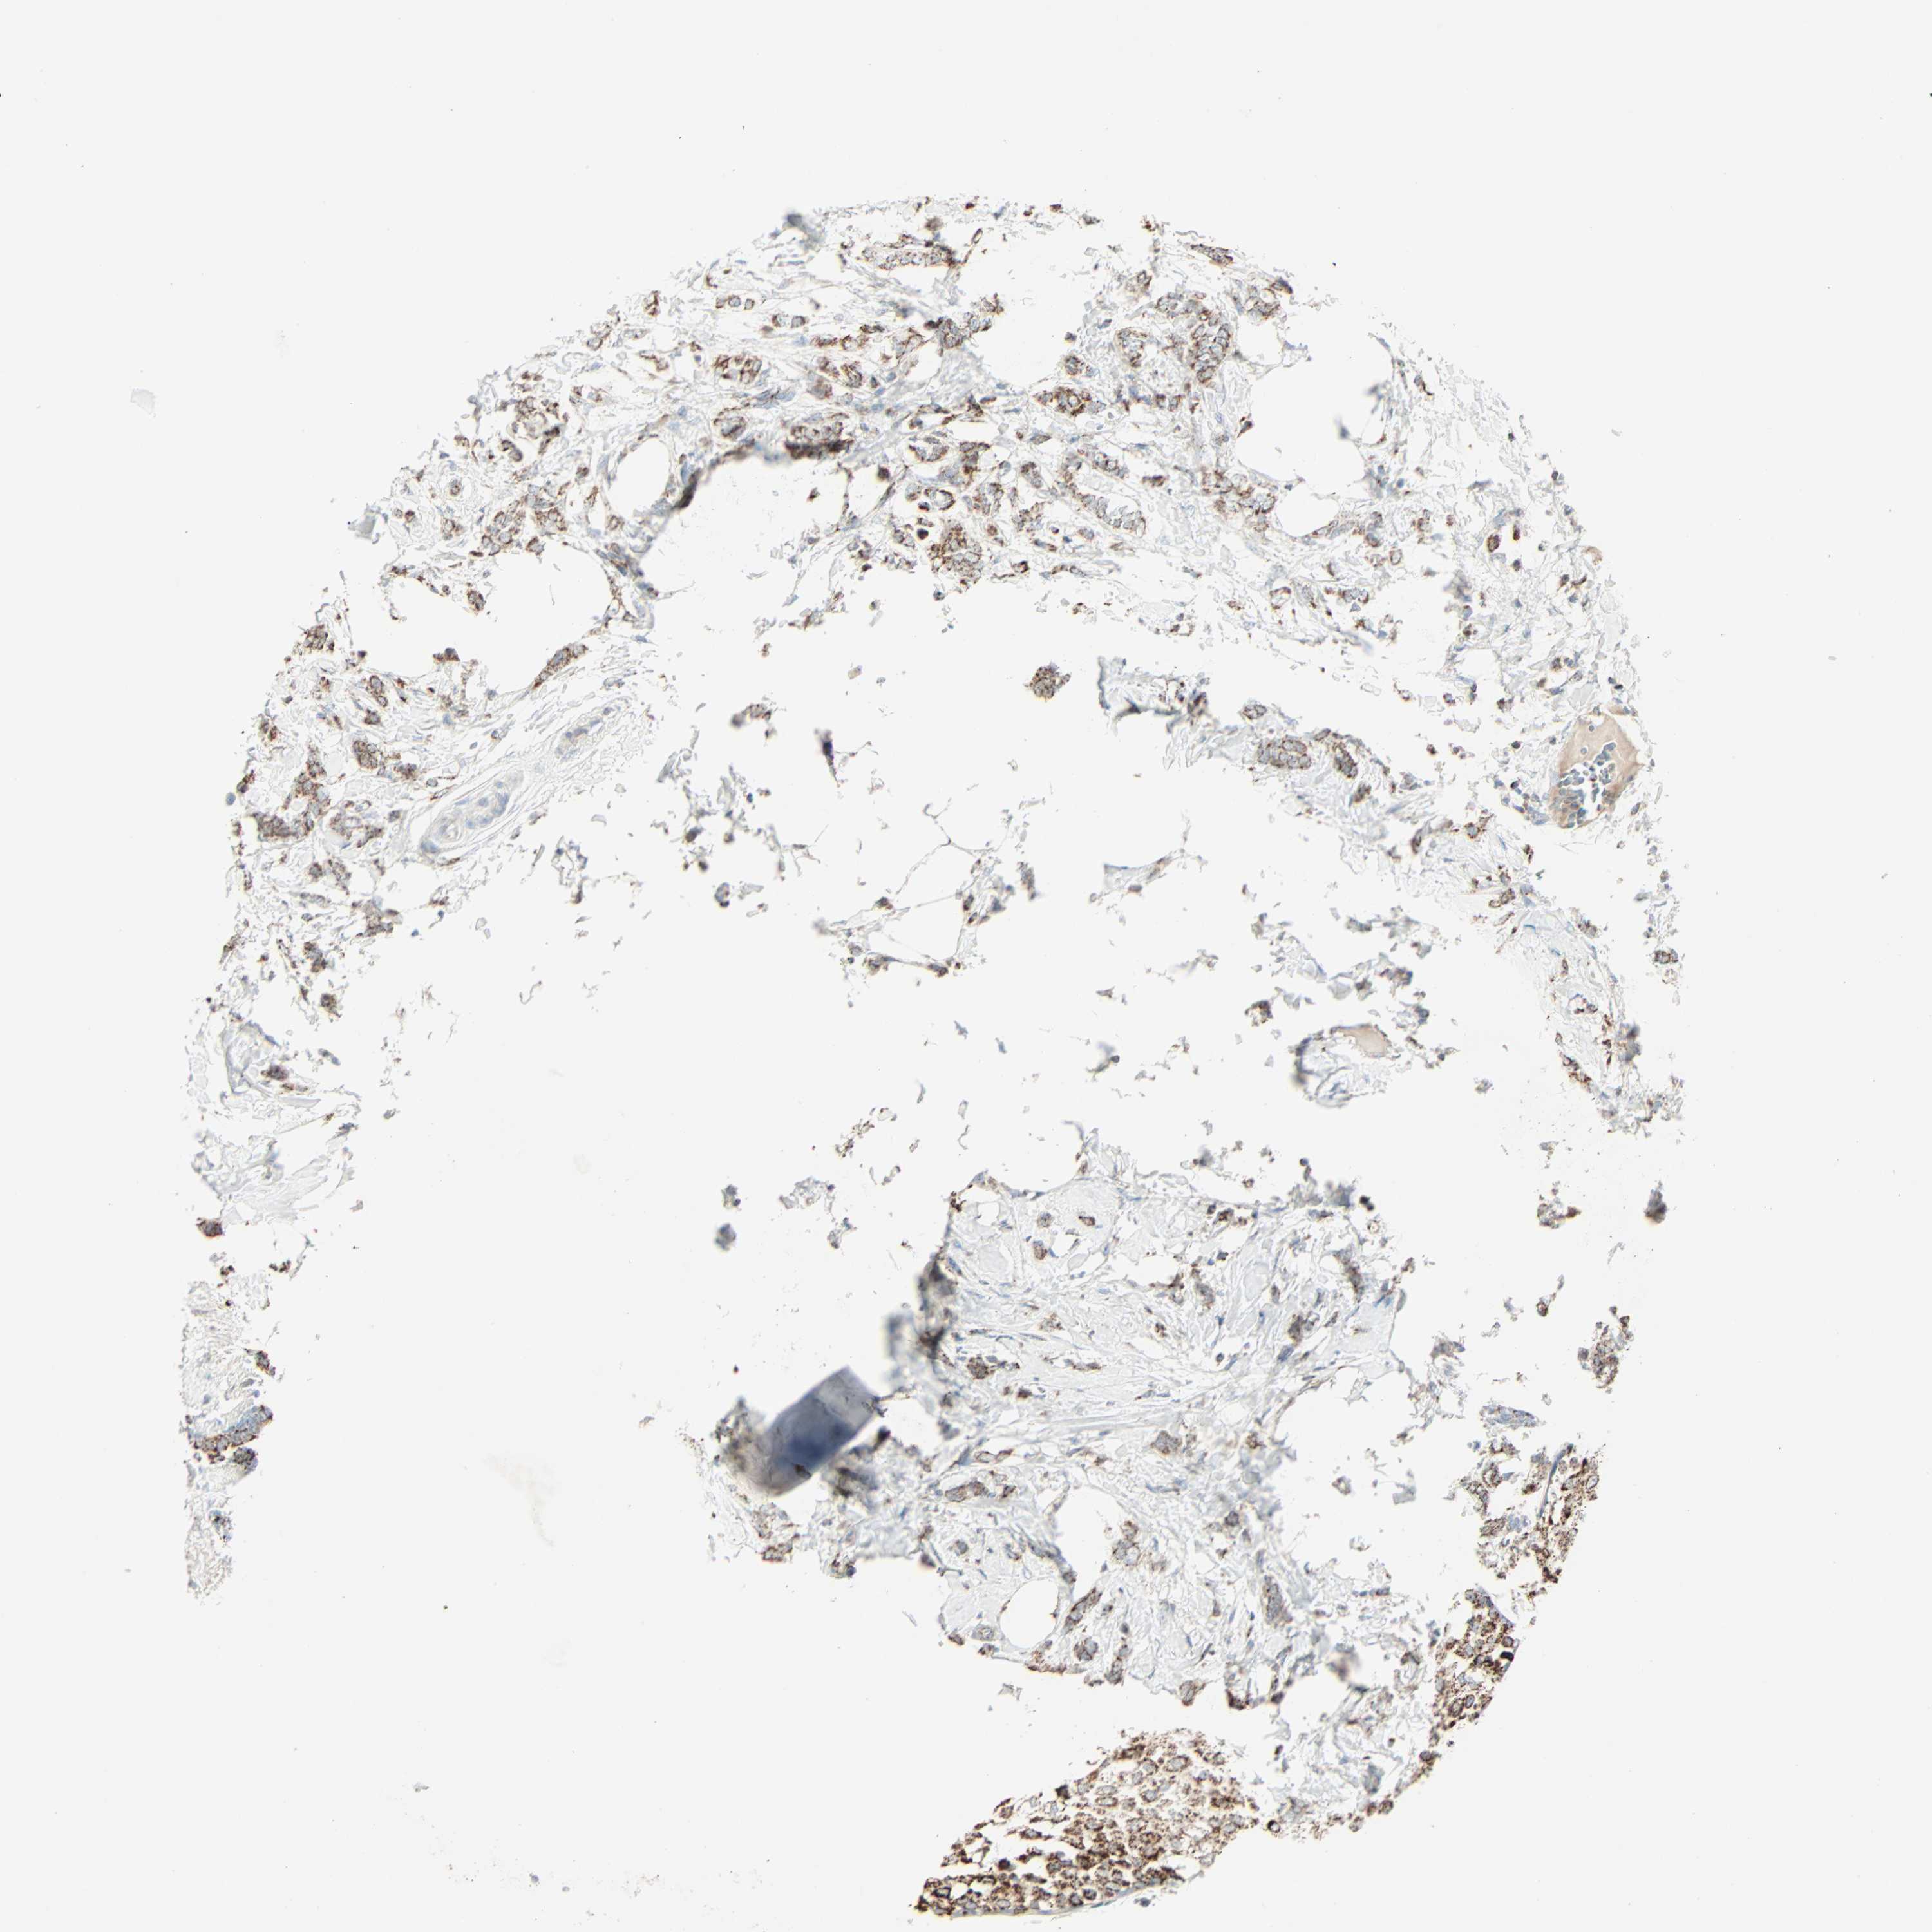

CANCER BREAST CANCER Show tissue menu

BRCA TCGA BRCA VALIDATION PROTEIN EXPRESSION

Breast cancer

Human cancer